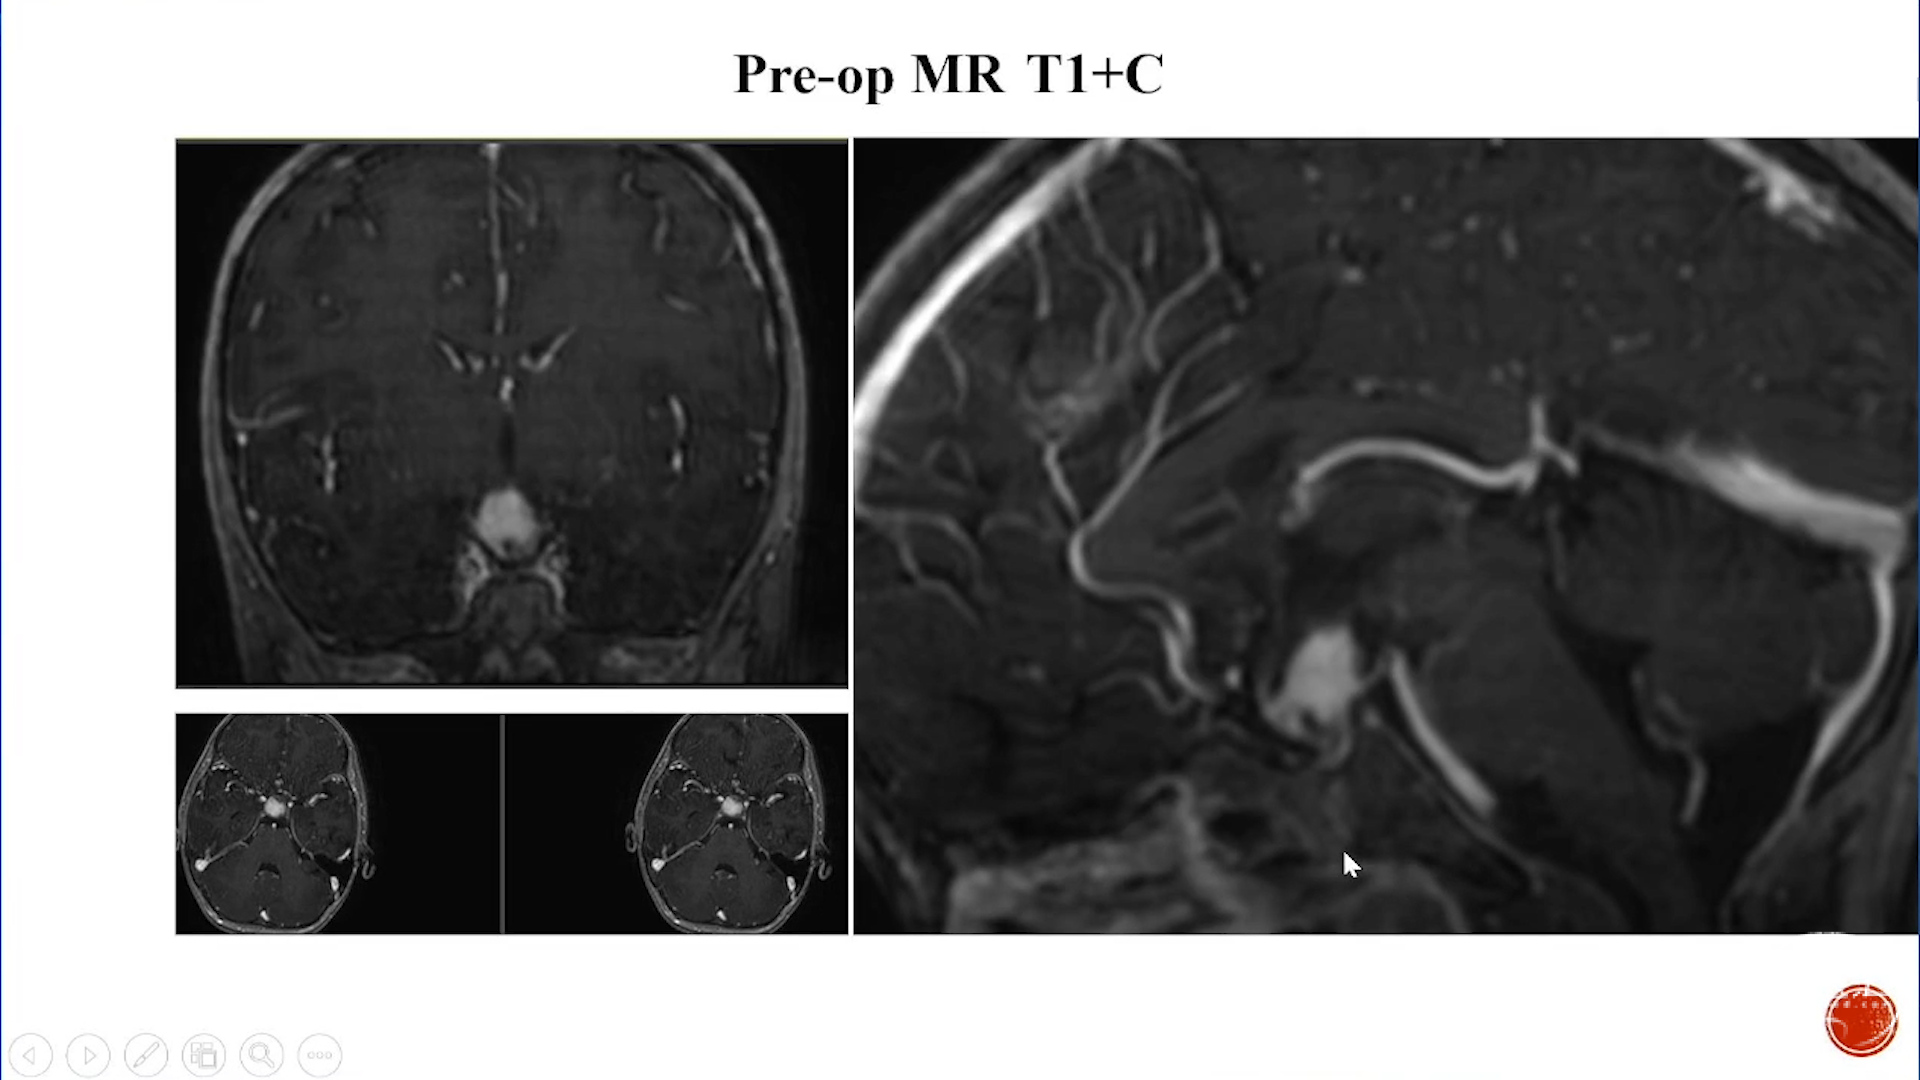

小脑星形细胞肿瘤

大脑半球儿童低级别胶质瘤